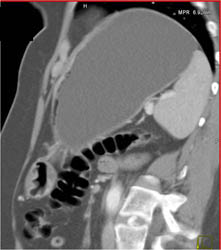

Antral Cancer